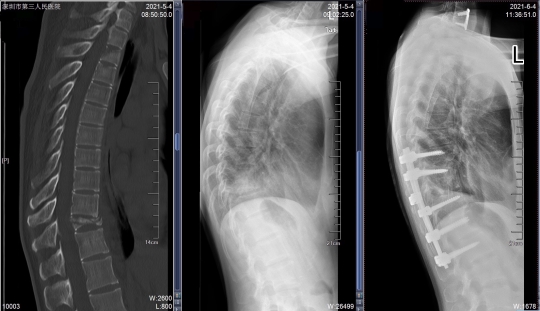

袁女士胸椎术前CT、DR及术后DR

稿件来源:深圳市第三人民医院 发布时间:2021-06-11 14:51:00近日,深圳国家感染性疾病临床医学研究中心/深圳市第三人民医院(南方科技大学第二附属医院)骨二科成功救治了一名多发骨结核患者。该患者刚到医院时呼吸困难、走路无力、胸背疼痛难忍,生活受到严重影响。深圳市三院骨二科为她量身定制手术方案,一次性完成胸椎等多个部位病灶清除的高难度复杂手术,耗时5个小时,出血量仅为300毫升。手术难度极高,在深圳尚属首例。

根据袁女士的病情,相关科室经过会诊,决定对她进行手术治疗。骨二科主任李宏伟提出,要一次完成3个手术:胸椎后路固定植骨融合术、经左侧第十肋开胸胸11椎体病灶清除椎管减压植骨融合术、经前路颈7椎体结核病灶清除减压植骨钢板内固定术。

这台手术对骨科医生的技术要求很高,同时完成胸椎前后路及颈椎前路手术风险很大,而且不仅要把控风险,还要尽力减少出血量。此前深圳尚无先例。

手术由李宏伟指导,黄志刚副主任医师治疗组进行,用时5个小时顺利完成,术中出血仅300毫升。术后,袁女士的胸背疼痛及下肢无力的情况完全缓解,精神状况和食欲都改善了许多。